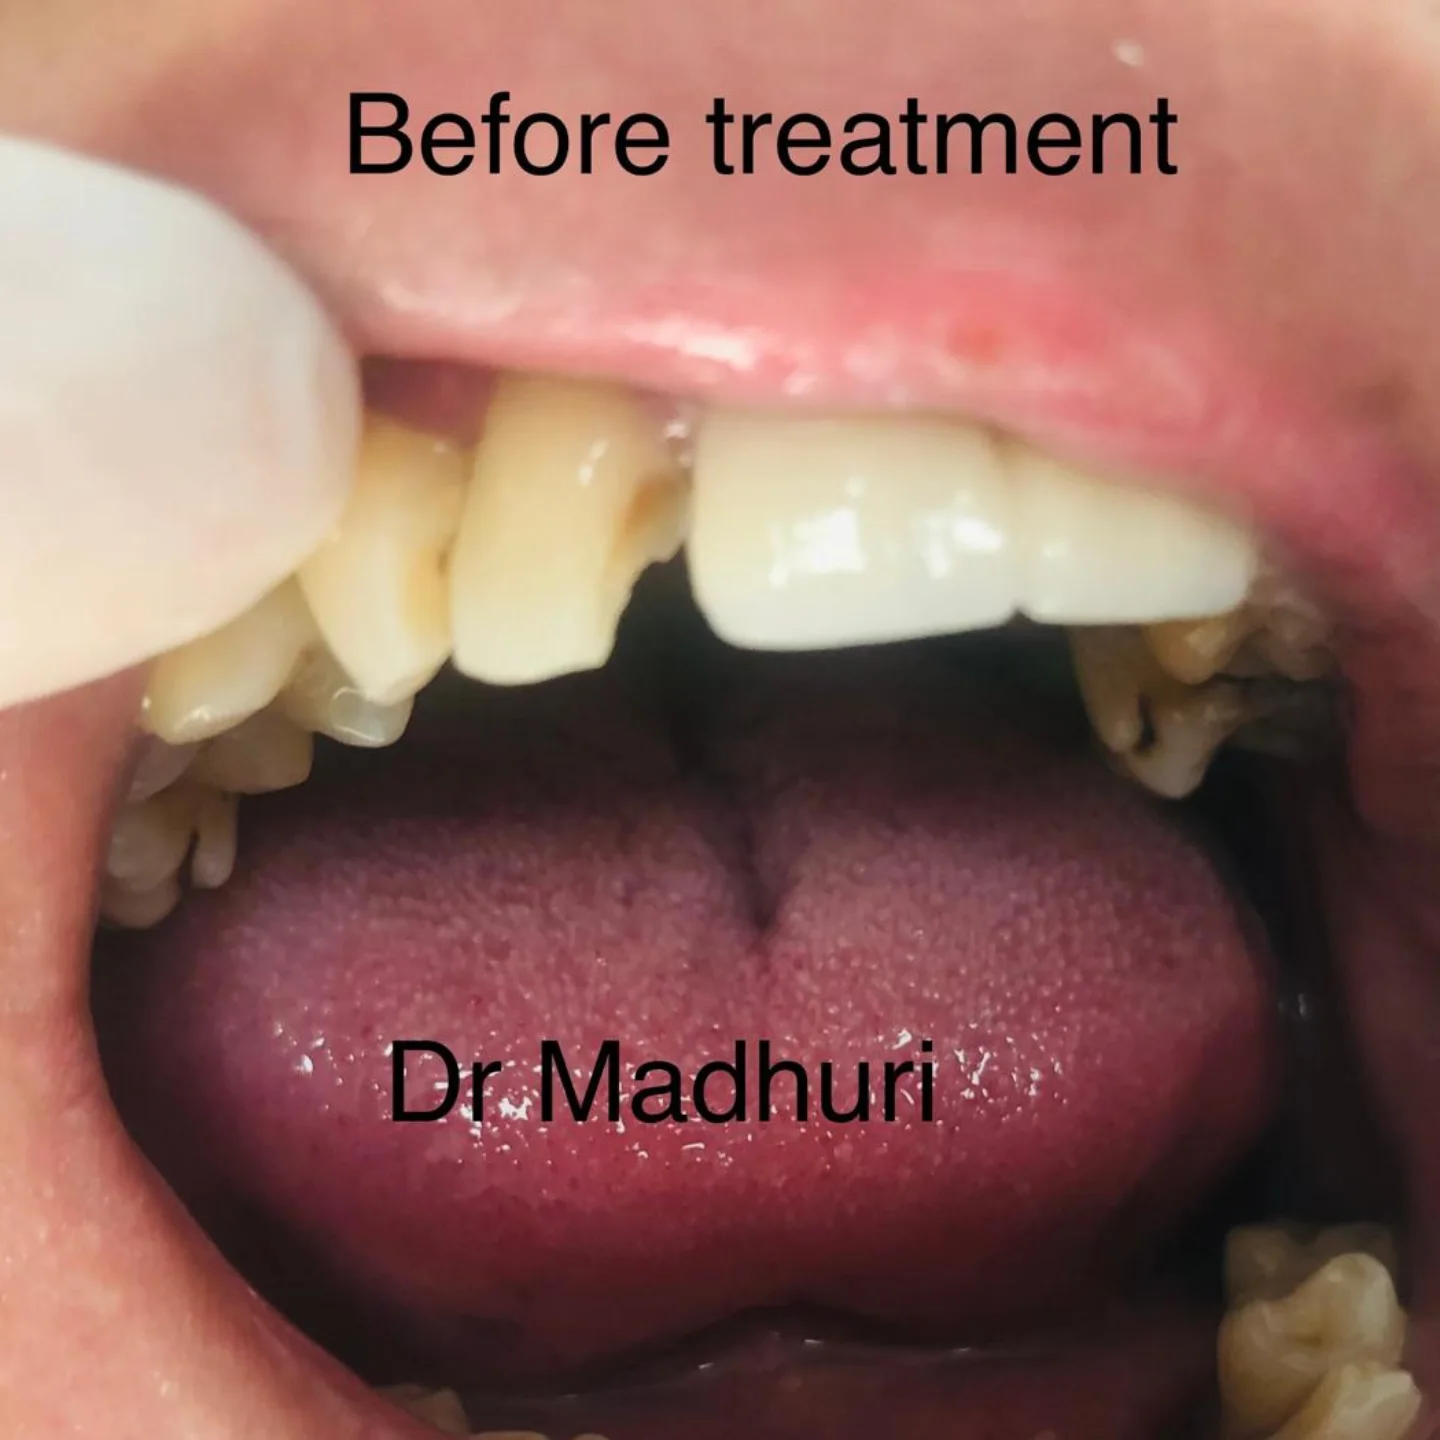

Explore Our Clinical Dental Gallery

Welcome to our official treatment gallery, showcasing the real results, smile transformations, and advanced dental care delivered by Dr. Madhuri. We believe that a picture is worth a thousand words when it comes to the art and precision of modern dentistry. Review our comprehensive visual portfolio below to see how our dedicated care helps patients achieve healthy, beautiful, and confident smiles.